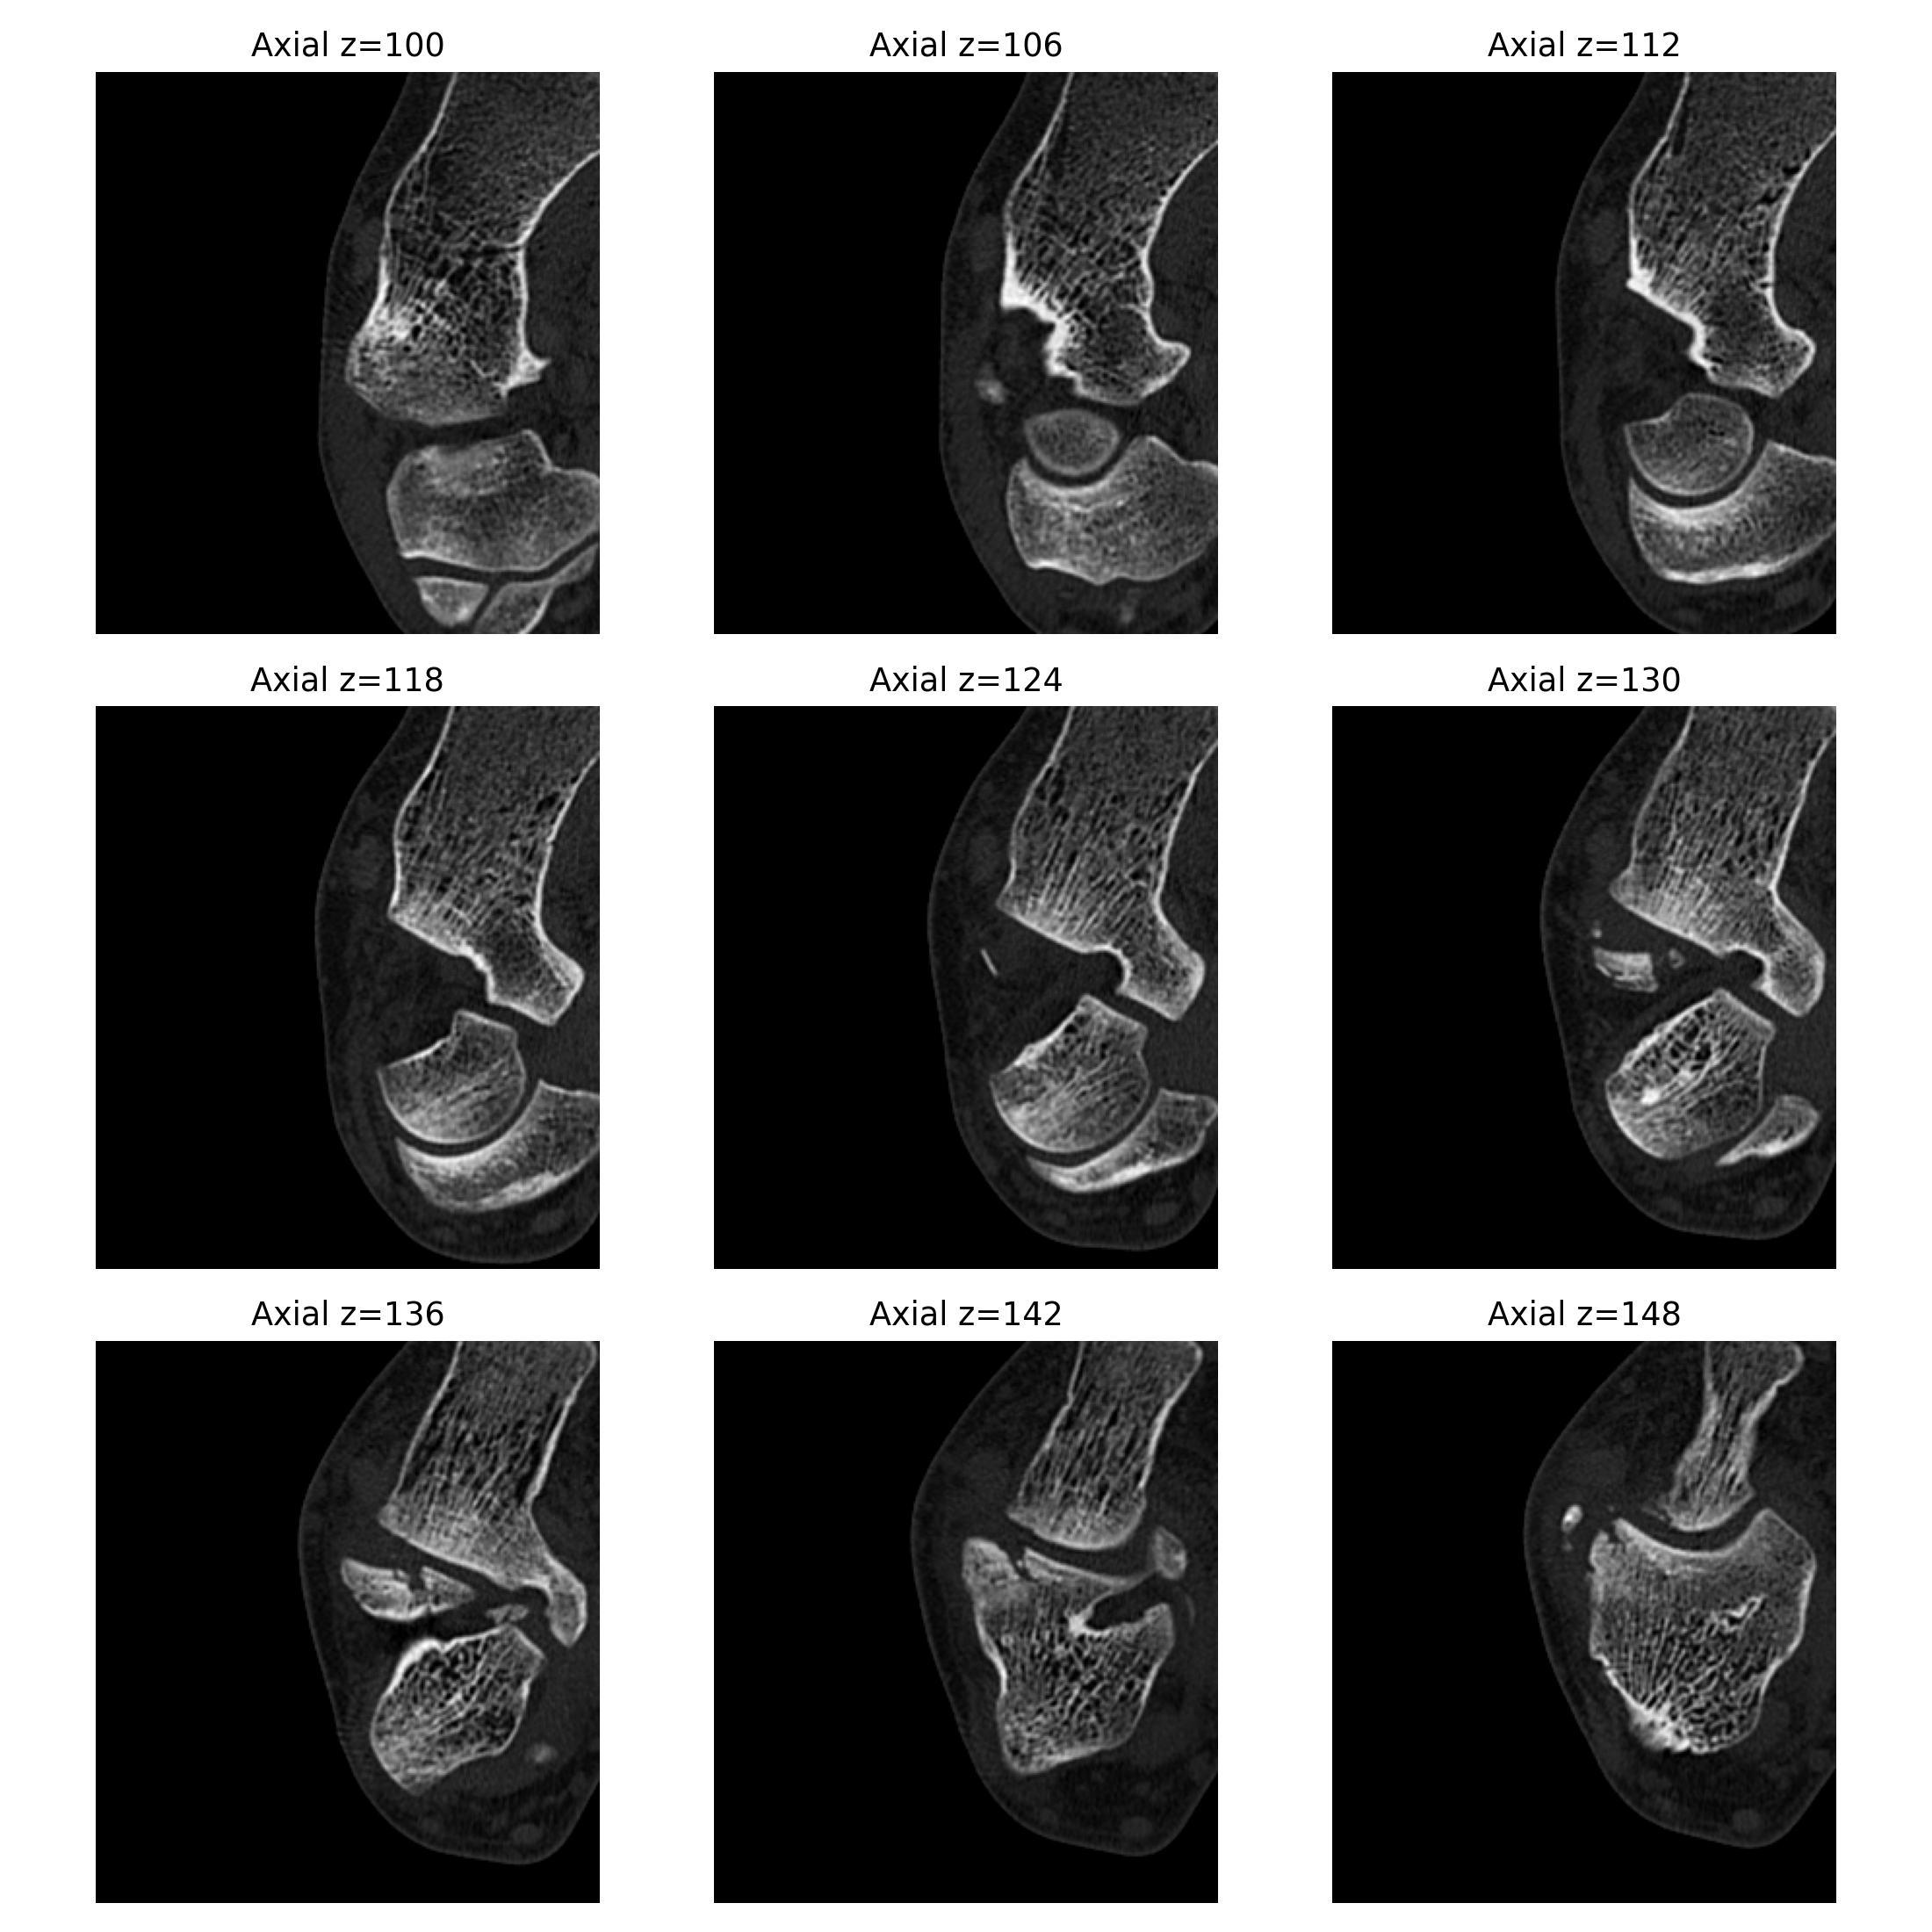

基于 2026-04-02 右踝无对比 CT 原始 DICOM 的辅助分析。核心问题是: 右踝外侧、距骨外侧突及距下关节外侧附近存在高概率关节内骨性损伤, 表现更接近单板滑雪常见的 snowboarder’s fracture。

- 异常位置集中在外踝前下方、距骨外侧突附近、距下关节外侧缘附近。

- 冠状位、矢状位和三维辅助重建里都能反复看到局部骨性不规则和分离感。

三维与关键切面

三维图更适合看骨片和关节面的空间关系;真正判断骨折线、关节面台阶和位移, 仍然要以原始 CT 切面为主。